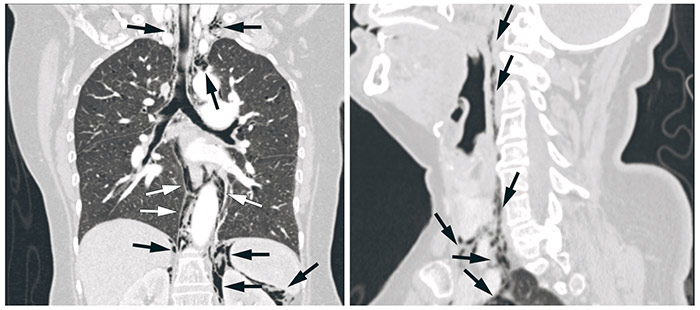

Ved undersøkelse på legevakten var hun subfebril, oropharynx var uten anmerkning og hennes abdomen var bløt med normale tarmlyder, men diffust øm ved palpasjon. CRP var 200 mg/l. Muligheten for en rektal perforasjon etter polyppektomi ble overveid, og det ble gjort en røntgen oversikt abdomen som ga mistanke om fri luft retroperitonealt. En CT-undersøkelse av collum, thorax og abdomen bekreftet fri luft (se piler) i retroperitoneum, mediastinum og retrofaryngealt, hvor sistnevnte forklarte hennes halssmerter. Pasienten ble behandlet konservativt med intravenøs antibiotika og faste, og ble utskrevet fra sykehuset seks dager senere.

Forklaringen på at luft kan spre seg på denne måten er de potensielle anatomiske rommene som strekker seg fra retroperitoneum, gjennom mediastinum og opp til halsen. Den økende bruken av diagnostiske og terapeutiske endoskopier gjør at man bør være oppmerksom på komplikasjoner, og at perforasjon med retroperitoneal luft kan gi uventede symptomer (1).